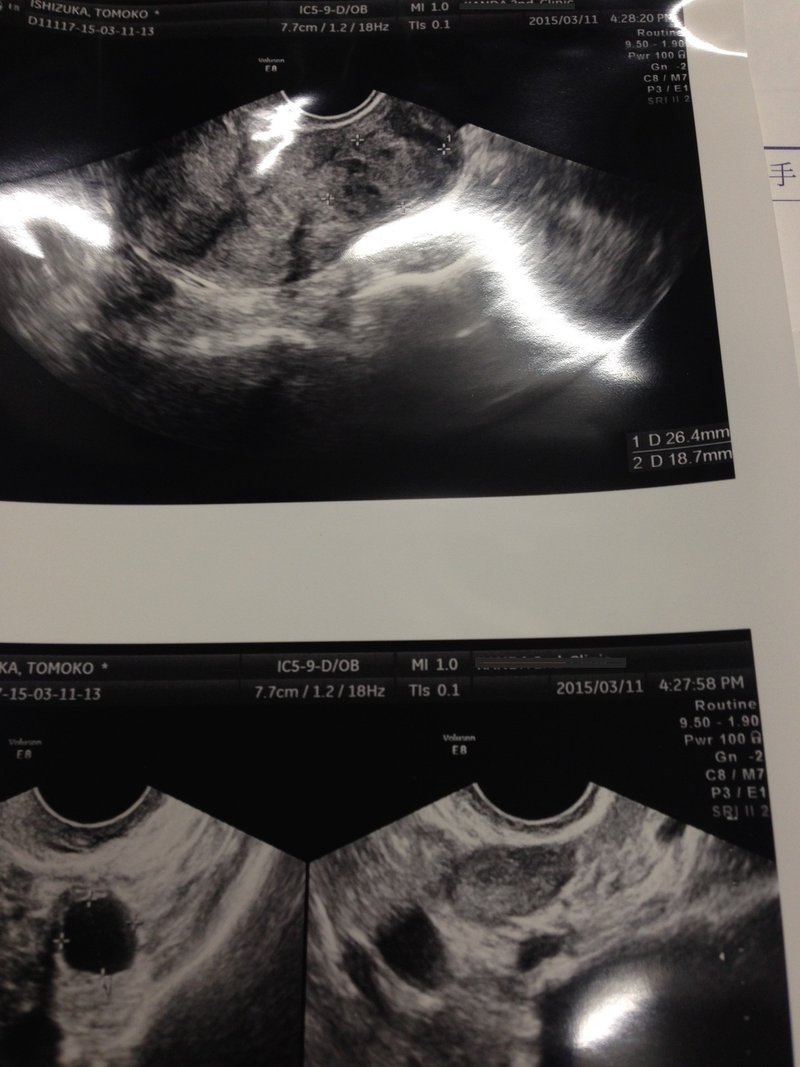

10個以上ごろごろあった子宮筋腫 今回の撮影で2個だけになっていた いしづかとも Note